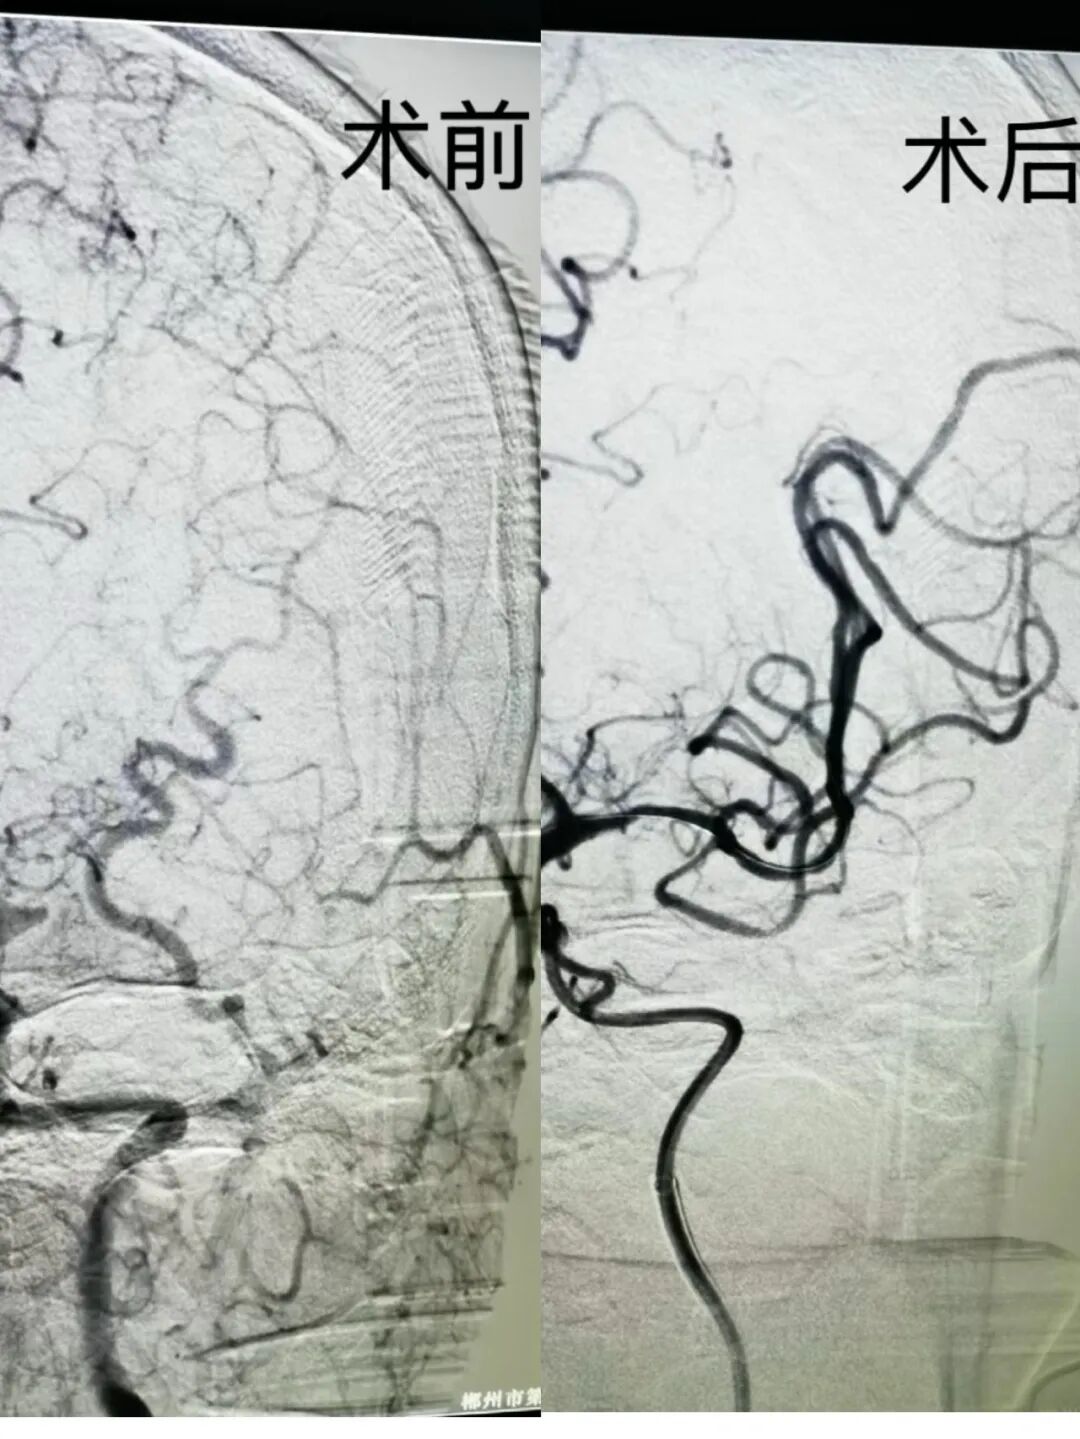

“这是一例典型的大血管闭塞性脑卒中,静脉溶栓后血管再通不理想,需要立即进行血管内取栓治疗。”神经内科副主任医师蒋龙飞迅速评估病情后得出结论。时间就是大脑,每延迟一分钟,脑细胞死亡数量就以百万计。科室立即启动脑卒中应急流程,通知介入团队、麻醉科、护理团队做好急诊手术准备。神经内科唐惠祥主任迅速组织多学科会诊,影像中心优先为患者完成头颅CTA+CTP检查,证实了左侧大脑中动脉闭塞的诊断,且存在明显的缺血半暗带——这意味着如果及时开通血管,脑组织还有挽救的机会。所有流程无缝衔接,从患者入院到进入介入手术室,用时不到一小时。

手术顺利结束,患者被转入神经重症监护室。术后第二天,患者神志转清,右侧肢体肌力明显恢复。